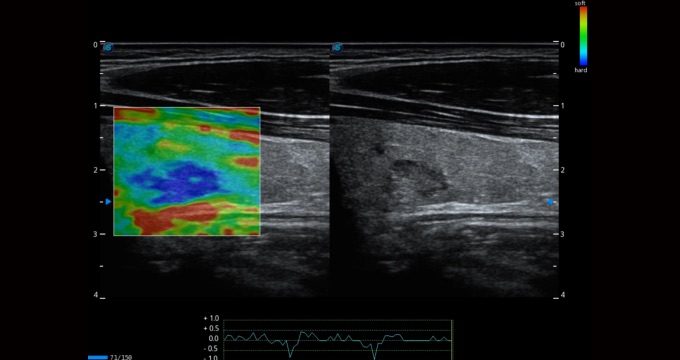

弹性成像支持多把探头,满足全面的临床应用。无需高频度外力作用可真实反映组织的形变,具有良好的重复性,帮助医生早期洞察潜在的病理学特征。